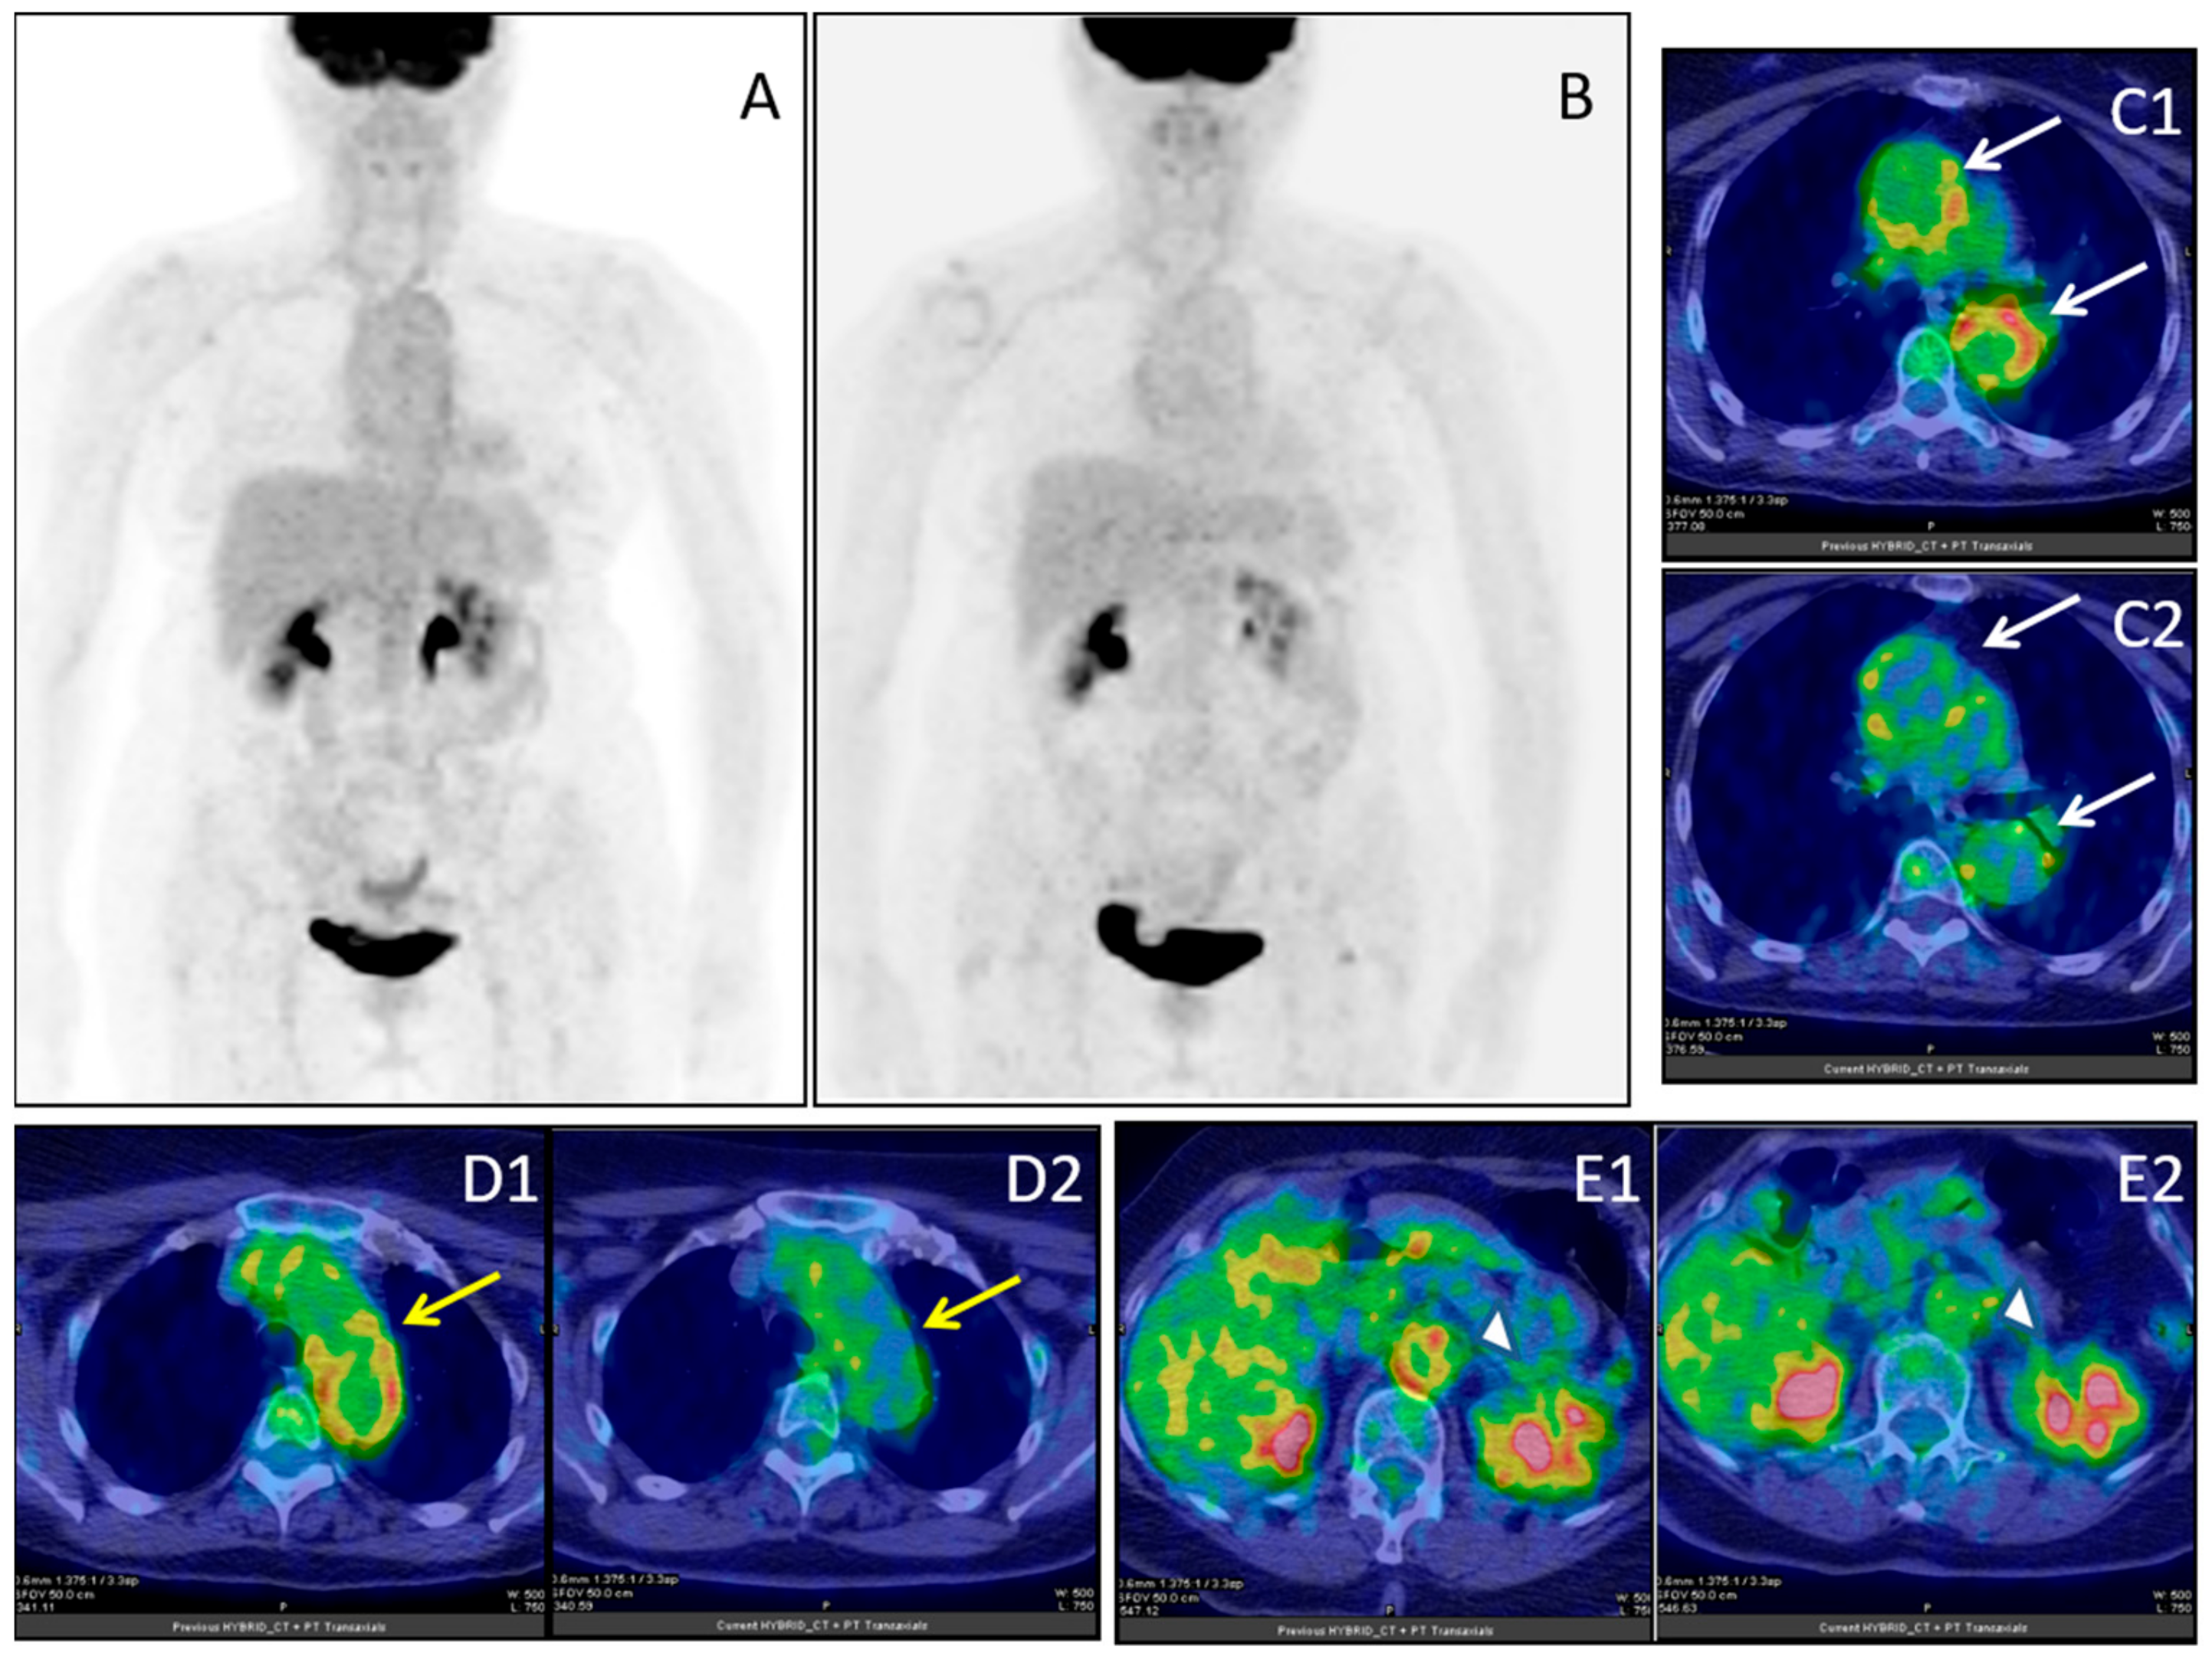

- Ankrah, O.A.; Span, L.F.R.; Klein, H.C.; de Jong, P.A.; Dierckx, R.A.J.O.; Kwee, T.C.; Sathekge, M.M.; Glaudemans, A.W.J.M. Role of FDG PET/CT in monitoring treatment response in patients with invasive fungal infections. Eur. J. Nucl. Med. Mol. Imaging 2019, 46, 174–183. [Google Scholar] [CrossRef]